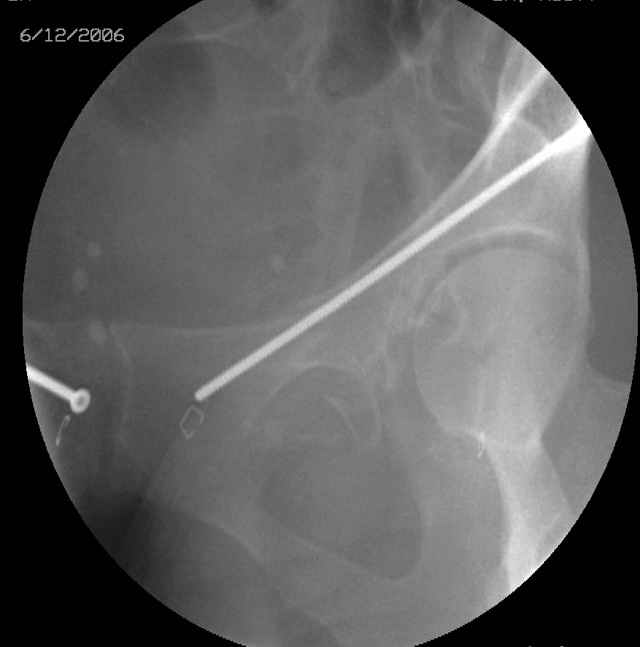

Prone Inlet

OK, now we're inserting the drill percutaneosuy using a sleeve. This fluoro shot is not for this patient (notice no clamp) but I was too lazy to go searching the PACS for one with the clamp on, so pretend...I'll save the next ones and send along...the imaging is the same and the clamp doesn't obstruct imaging other than very rarely...you can always tilt the C-arm a bit to clear it if the clamp obstructs the exact spot that you'd like to see. We'll assume that everyone knows the safe zone for a medullary ramus screw. Use a calibrated drill and sleeve of known length to simplify your life...or use Alex's fancy cannulated screws...I like 3.5mm screws because the oscillating 2.5mm drill bounces and remains intraosseus when it oscillates and contacts endosteal cortical ramus... so will the screw, and like a long bent screw IF the fracture is clamped... if unclamped, when the screw contacts the endosteum, it pushes the reduction apart instead of bouncing. The big 7mm cannulated screws fit few patients and extrude...we very rarely use them any more...you'll see an old one later.